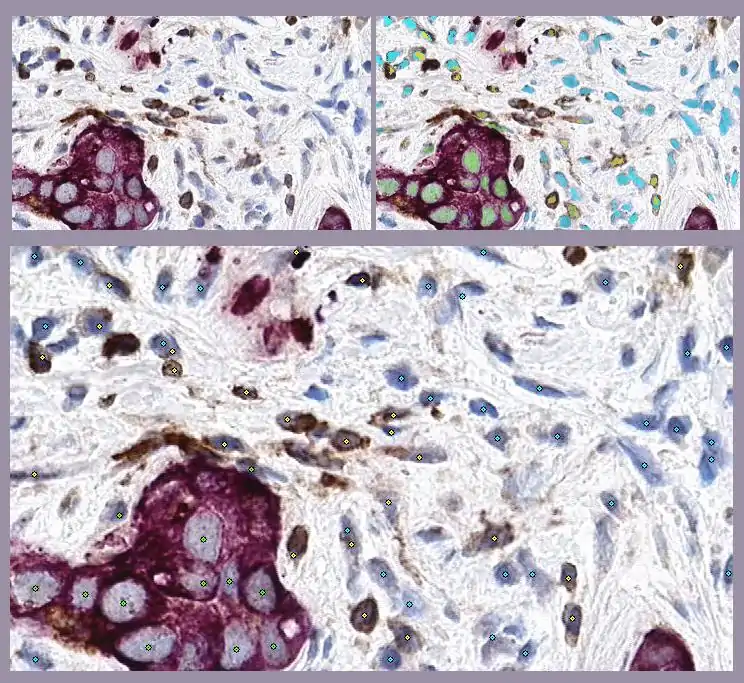

This example illustrates GemIdent's ability to find multiple phenotypes in the same image: the raw microscopic image of a stained lymph node (top left) from the Kohrt study,[2] a superimposed mask showing the pixel classification results (top right), and finally the image marked with the centroids of the objects of interest - the cancer nuclei (in green stars), the T-cells (in yellow stars), and non-specific background nuclei (in cyan stars).